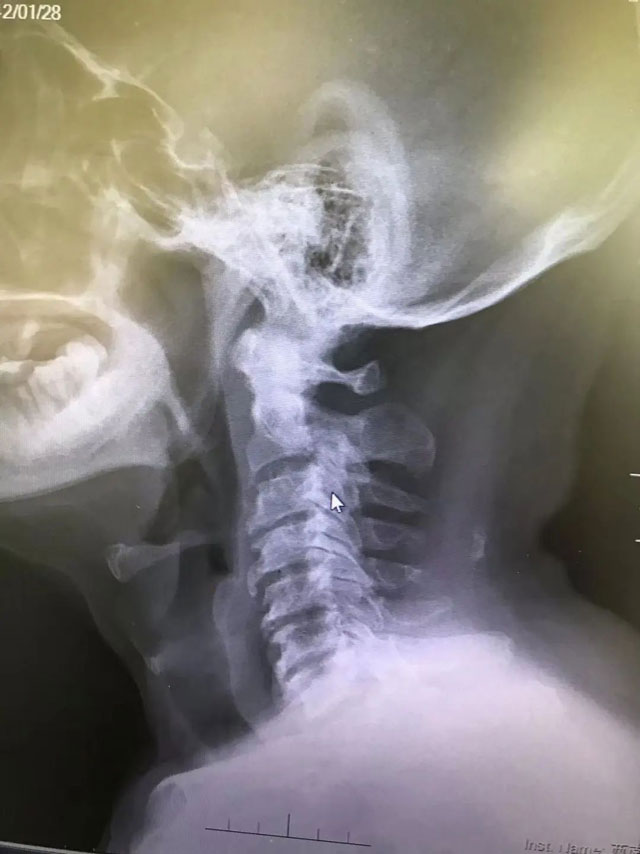

术前

王清介绍,王爷爷的纤维瘤位于颅颈交界处,位置深在,解剖结构极其复杂,紧邻重要的生命中枢,加上王爷爷已是高龄,伴有心脏病、糖尿病及肾功能不良,手术风险很高。目前,国际国内文献记载过此类疾病的不超过十例,且没有书面成功经验可借鉴。但若不做手术减压,患者将在轮椅上度过余生,一两年内可能会因呼吸困难、大小便功能障碍而死亡。

该患者是82岁高龄的王爷爷。一年前,王爷爷出现肩颈疼痛、四肢麻木无力等症状。今年初,王爷爷在其他医院检查时,因年纪大,且身体出现的症状不严重,再三思虑后没有接受医生让其做手术的建议,选择保守治疗。近段时间,王爷爷不仅四肢发麻发软、声音嘶哑、喝水容易呛咳,走路也成了问题,于是前往西南医科大学附属医院就医。